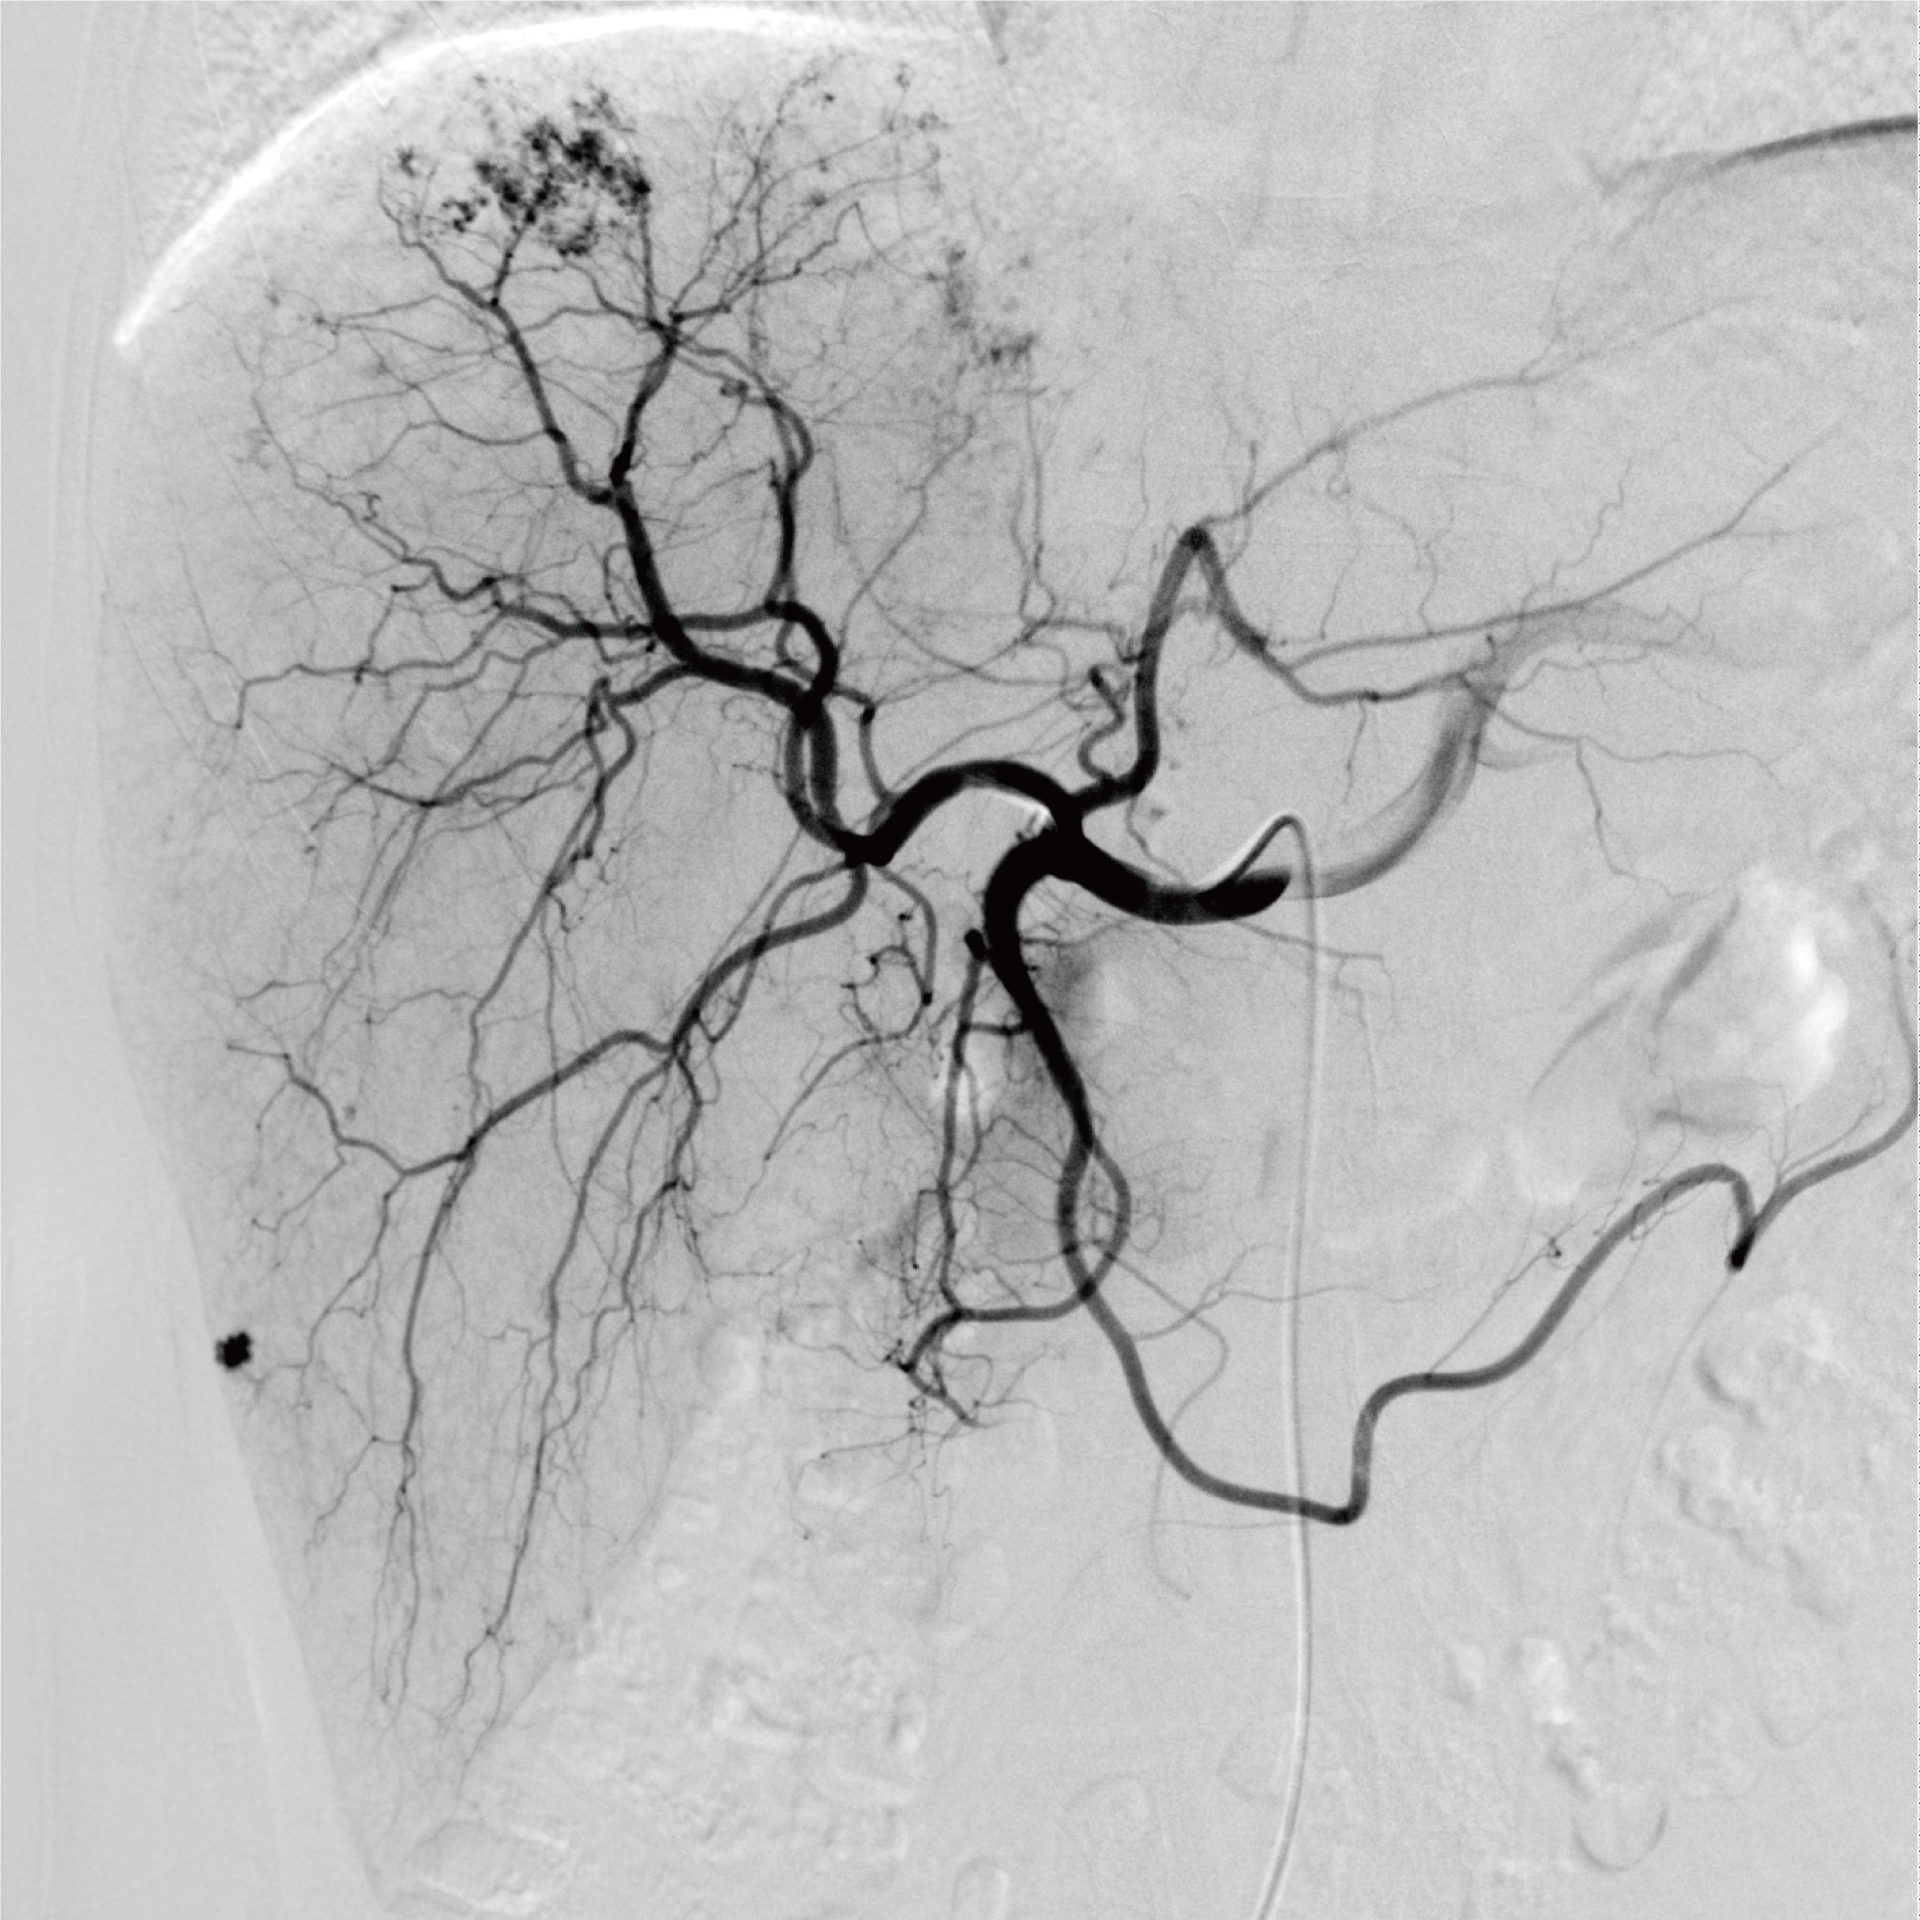

唯邁醫(yī)療極光DSA肝臟造影減影圖

導(dǎo)管插入肝動(dòng)脈后造影,顯示肝內(nèi)腫瘤供血豐富。

經(jīng)肝動(dòng)脈化療栓塞(TACE)后再次造影,顯示腫塊已經(jīng)被完全栓塞。